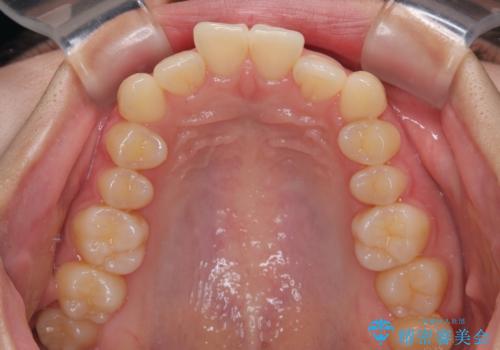

- 上下前歯のデコボコを気にして来院された患者様です。

ワイヤー矯正でもマウスピース矯正でも可能でしたが、短期間で、自身の手を煩わせることなく治療を行いたいとのことで、ワイヤー装置にて矯正治療を行うこととしました。

舌の突出癖により、出っ歯仕上がりとなる可能性がありましたが、舌のトレーニングを頑張っていただき、1年強で終えることができました。